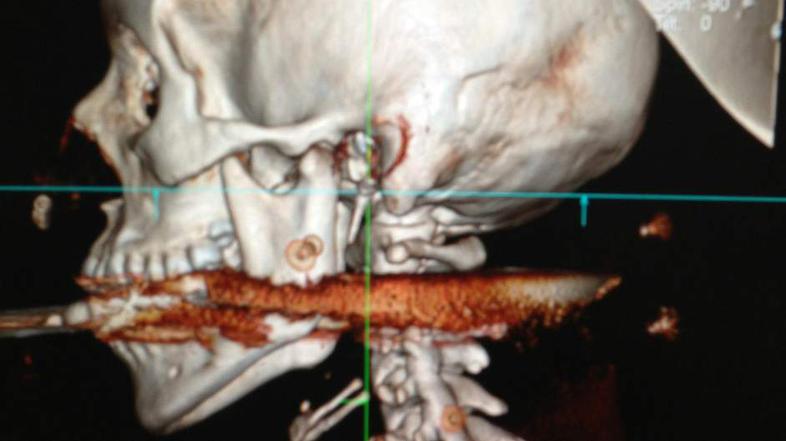

Brazilka harpuna nesreča Rio de Janeiro state health department

Neko Brazilko je mož med čiščenjem harpune ponesreči ustrelil in jo zadel v usta. Harpuna je prebila njeno hrbtenico, a je preživela, čeprav jo je od smrti ločil le en centimeter.

Elisangela Borborema Rosa je imela srečo v nesreči. Ko je mož v ponedeljek čistil harpuno, se je ta ponesreči sprožila in jo zadela v usta ter ji prebila hrbtenico. Osemindvajsetletnico so nemudoma odpeljali v bolnišnico, kjer so ji nudli nujno zdravniško pomoč. Nevrokirurg Allan da Costa je pojasnil, da je Elisangela izven smrtne nevarnosti in da bo popolnoma okrevala. "Če bi jo harpuna zadela en centimeter v drugo stran, bi postala tetraplegik, če pa bi šla za en centimeter v drugo smer, bi bila mrtva."